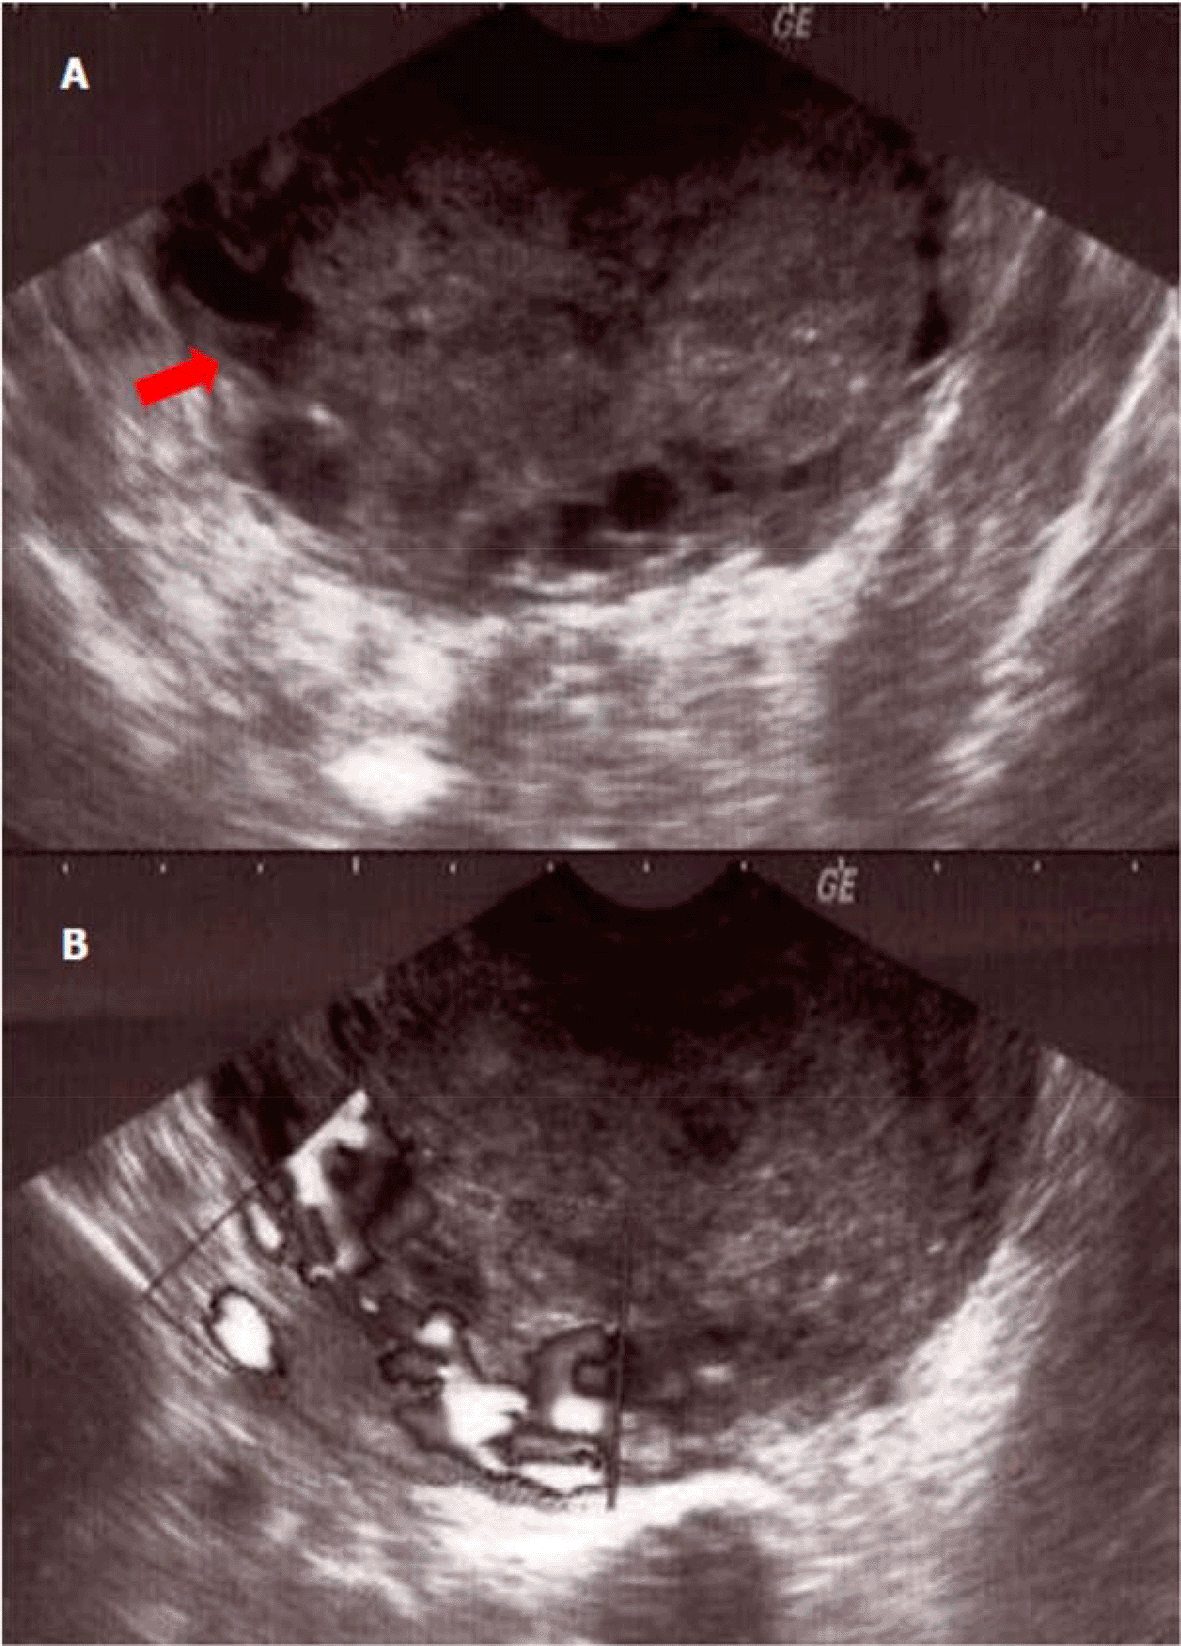

A physical examination revealed a fever of 39.5°C and abdominal tenderness. The blood pressure was 110/70 mm Hg and the heart rate was 82 beats/mn. Furthermore, there was no specific digestive or urinary symptom. Per speculum examination, the cervix was enlarged with purulent vaginal discharge. On digital pelvic examination, the uterus was increased in size accessed at 12 week gestation and its mobilization was painful. Blood tests showed an inflammatory syndrome with a C-reactive protein at 200 mg/l [≤ 6mg/l] and white blood cells at 17000/mm3 [4000-10000/mm3]. The beta-human chorionic gonadotropin (β-HCG) rate was positive at 674 U/l [< 5U/l]. The transvaginal sonography showed a large sized uterus containing an echogenic heterogeneous endometrial mass, vascularized on Doppler examination. This process seemed to invade the myometrium in part. In addition, ultrasound showed an average effusion in the Douglas' pouch (Figure 1) with a probable left adnexal abscess.

(A) Echogenic tumor occupying the uterine cavity (arrow) with infiltration of the myometrium; (B) appearance vascularized tumor at color Doppler.